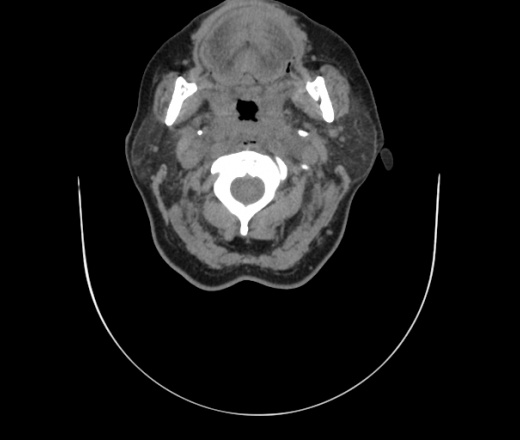

Женщина поступила в х/о спустя 4 дня после того как при употреблении карася подавилась костью.

Наличие газа в средостении на протяжении тел С2-С6 (медиастинальна эмфизема); рыбная кость на уровне тела С6.

При всем уважении, но говорить о медиастинальной эмфиземе, оценивая мягкие ткани шеи, как-то слишком резко. На мой взгляд, это ретрофарингеальное пространство.

Согласен с Вами; конечно, наличие газа в клетчатке ретрофарингеального пространства (затмение с опечаткой..). К сожалению, процесс "продвигается" к медиастиниту. Но почему никто, не отмечает наличие рыб. кости; или это для Всех очевидно?

Кость то мы сразу выявили, размеры где то 17*2мм, но ее так и не получается найти в этой каше